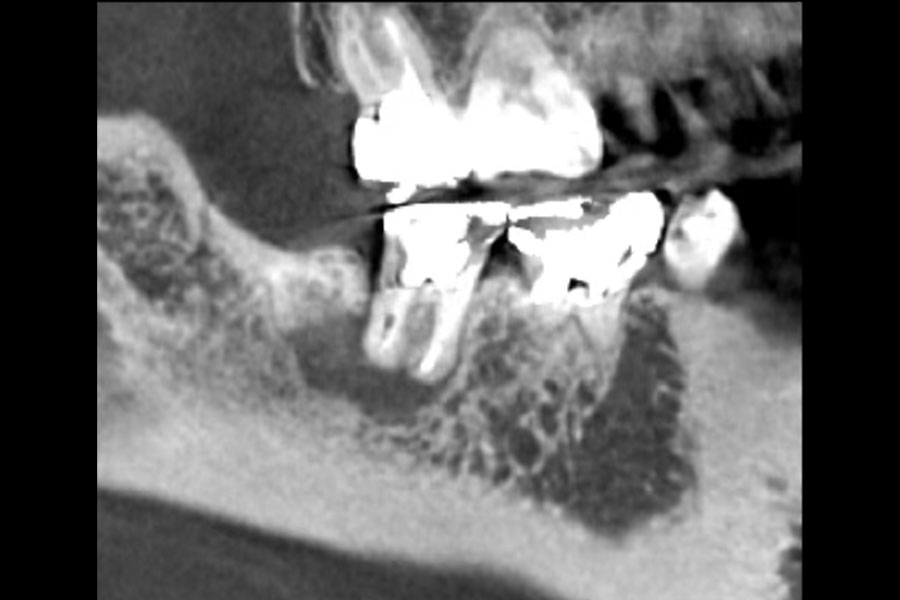

治療後